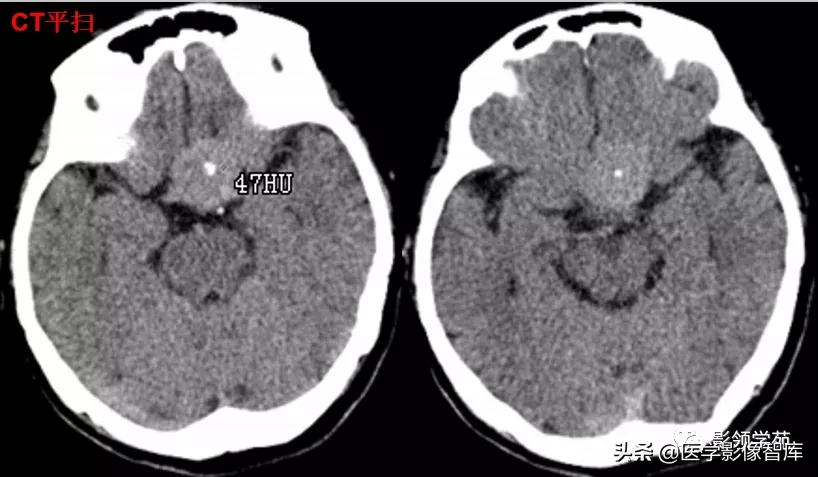

男 49岁, 肢端麻木2月。偶头晕头痛

鞍内及鞍上见一类圆形实性占位病变,边界尚清楚,密度欠均匀,CT值约41-58HU。垂体窝扩大,鞍背骨质稍变薄。

鞍上可见一类圆形均匀稍高密度灶,CT值约47HU,

边界清楚,其内见一小点片状钙化灶;继发鞍上池受压伴变性。